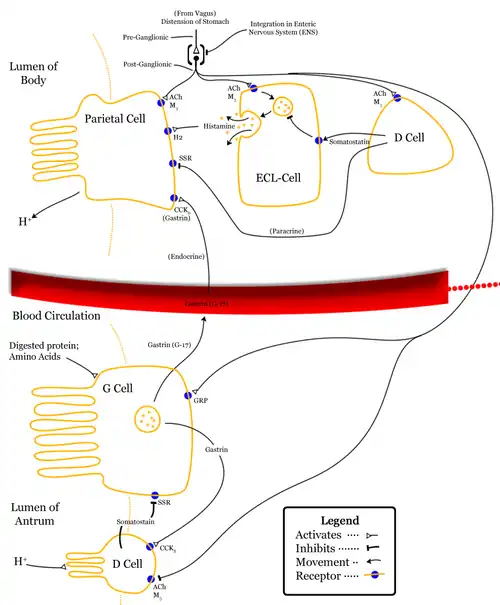

A G cell or gastrin cell is a type of cell in the stomach and duodenum that secretes gastrin. It works in conjunction with gastric chief cells and parietal cells. G cells are found deep within the pyloric glands of the stomach antrum, and occasionally in the pancreas[1] and duodenum. The vagus nerve innervates the G cells. Gastrin-releasing peptide is released by the post-ganglionic fibers of the vagus nerve onto G cells during parasympathetic stimulation. The peptide hormone bombesin also stimulates gastrin from G cells. Gastrin-releasing peptide, as well as the presence of amino acids in the stomach, stimulates the release of gastrin from the G cells. Gastrin stimulates enterochromaffin-like cells to secrete histamine.[2] Gastrin also targets parietal cells by increasing the amount of histamine and the direct stimulation by gastrin, causing the parietal cells to increase HCl secretion in the stomach. G-cells frequently express PD-L1 during homeostasis which protects them from Helicobacter pylori-induced immune destruction [3]